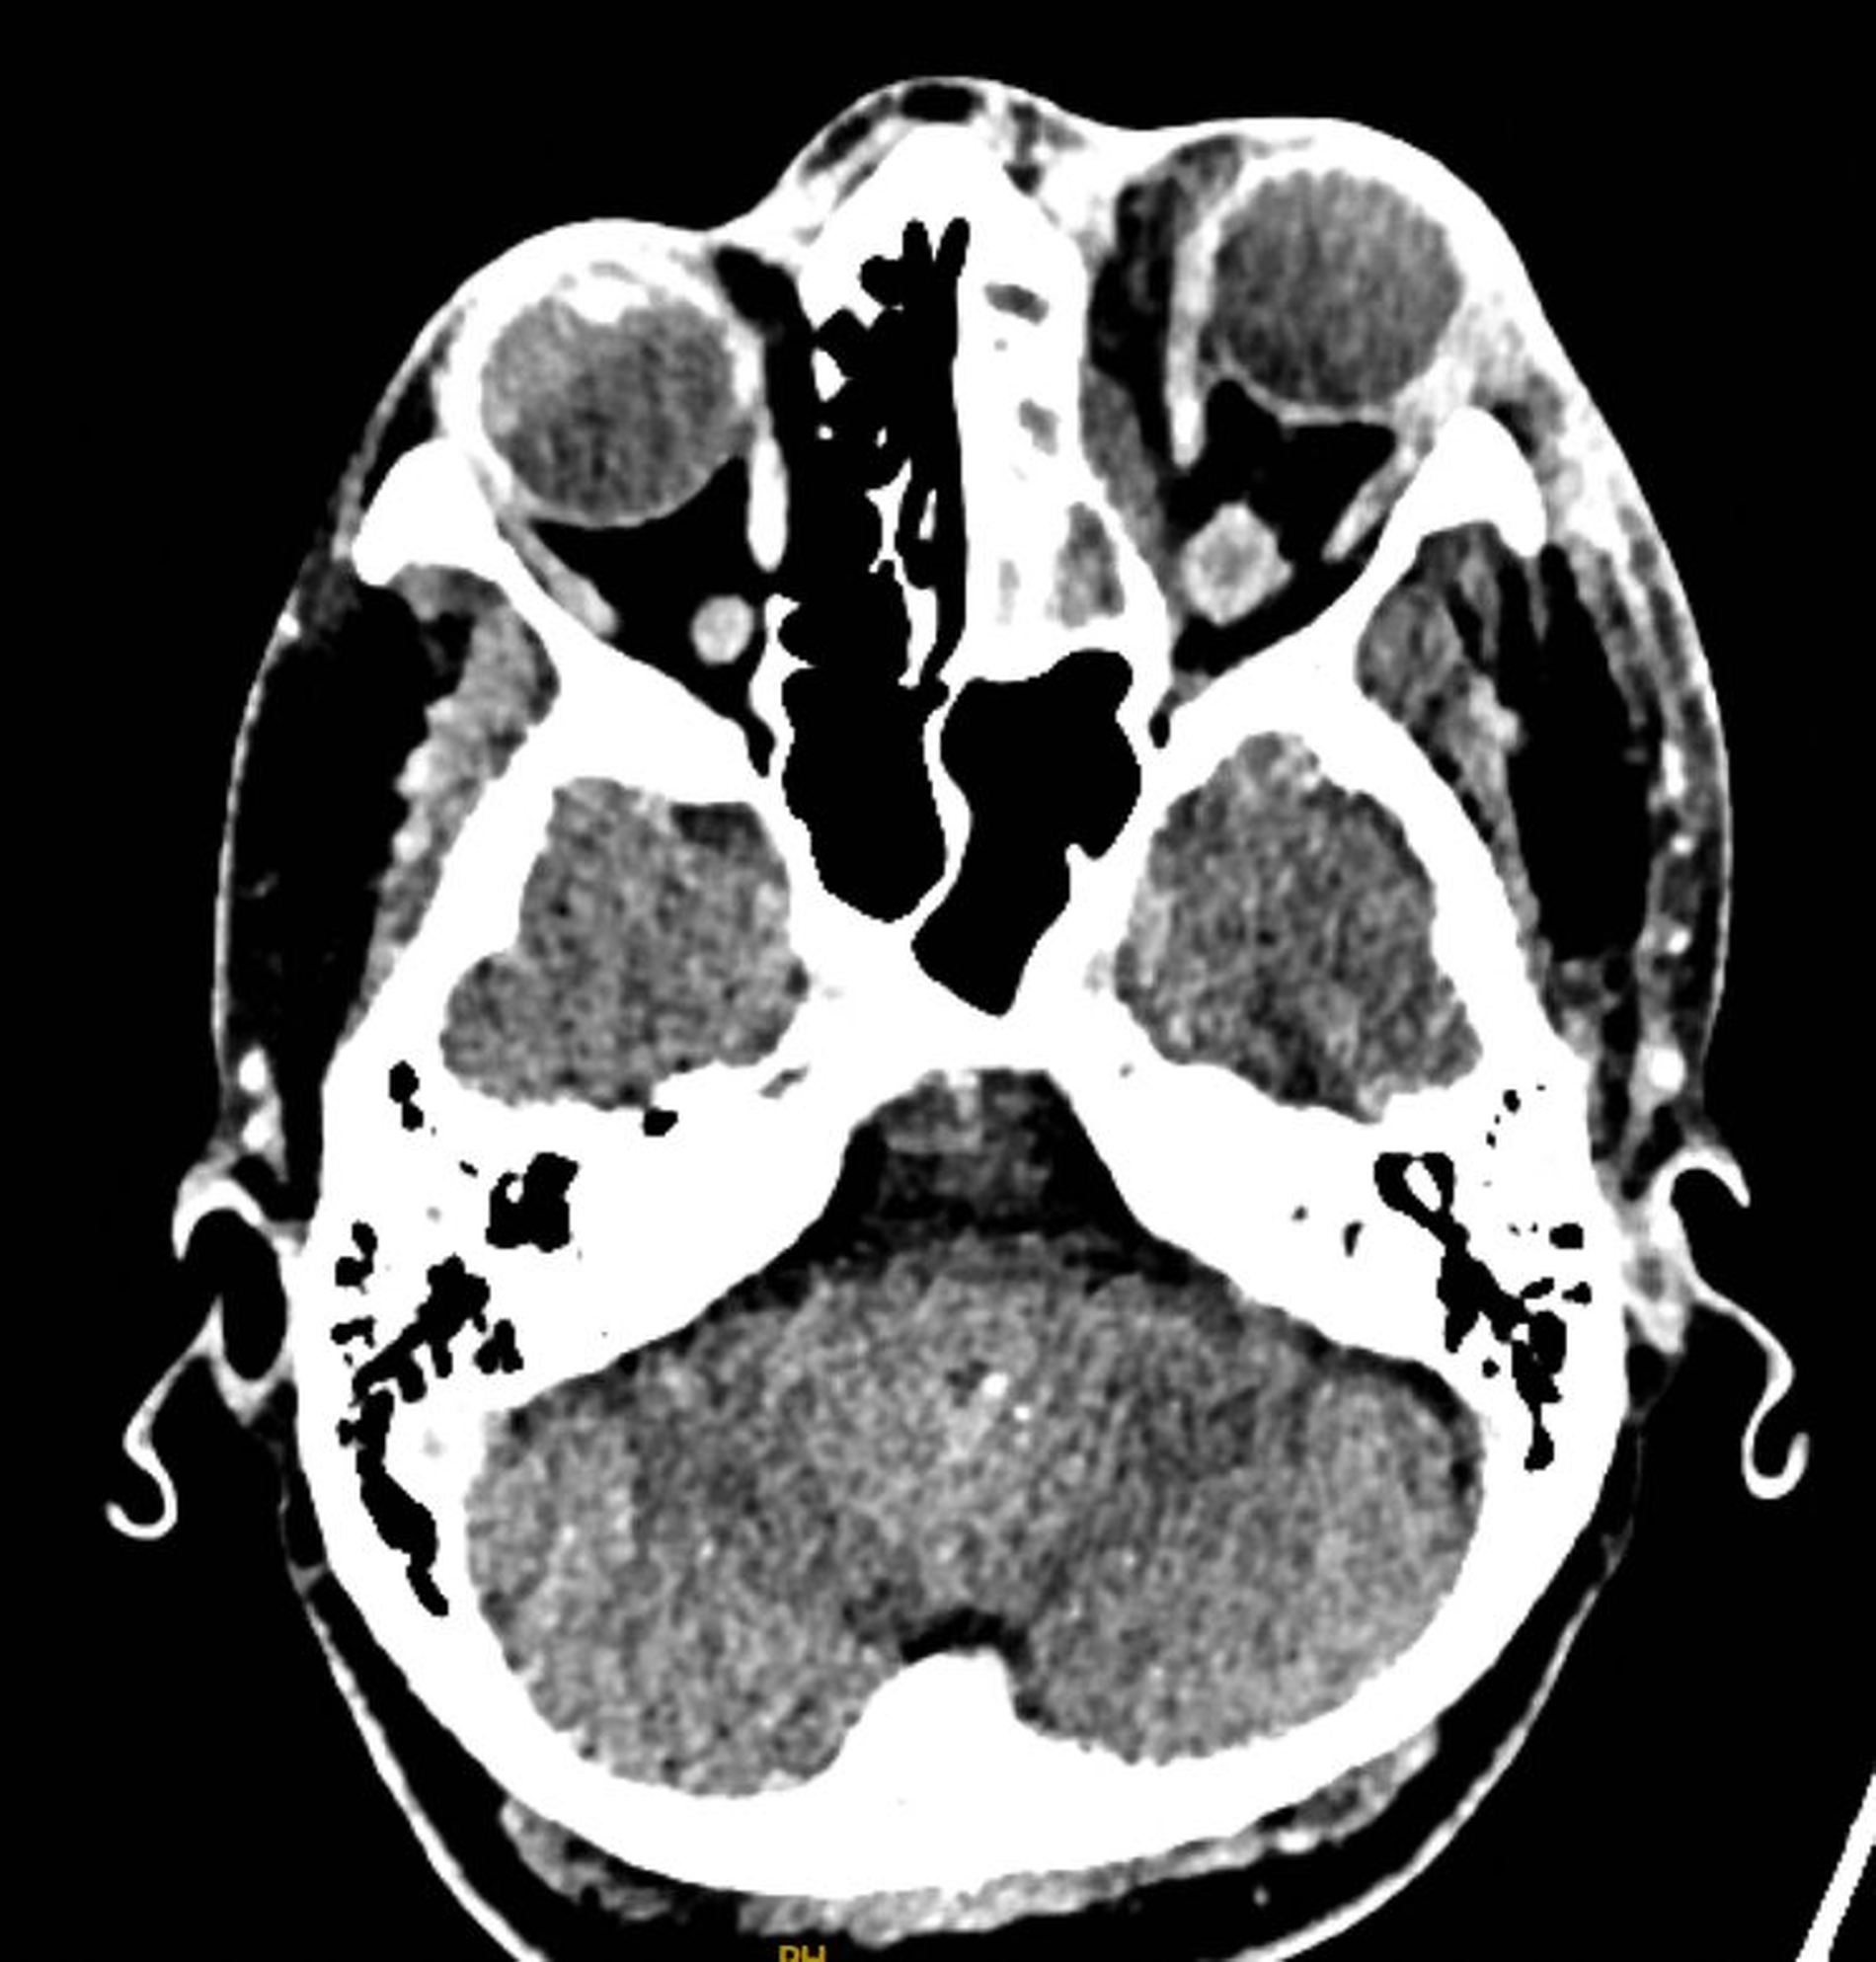

Im Unterschied zur DVT zeigte die Computertomografie mit Kontrastmittel einen medial lokalisierten subperiostalen Abszess in der linken Orbita mit umgebender entzündlicher Gewebereaktion, gedeutet als zumindest umschriebene Phlegmone (Abbildung 6). Die augenärztliche Untersuchung ergab einen Visus rechts von 1,0 und links von 0,63.

Anschließend wurde am selben Abend eine endonasale endoskopische Nasennebenhöhlenoperation links mit Uncinektomie, Kieferhöhlenfensterung Typ 3, anteriorer Ethmoidektomie und transethmoidaler Entlastung des Orbitaabszesses durchgeführt (Abbildung 7). Intraoperativ zeigte sich neben dem subperiostalen Abszess auch eine intraorbitale Abszesskomponente jenseits der Periorbita.